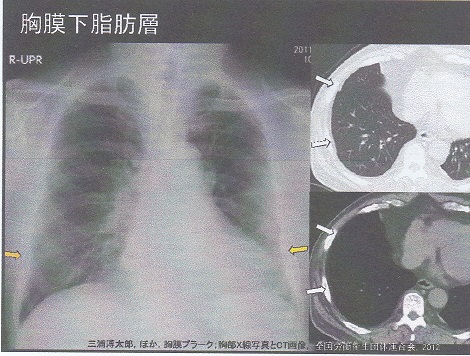

石綿による胸膜プラークと鑑別が必要な病態としては以下のものがある。

① 結核性胸膜炎後の石灰化病変

② 肺尖肥厚

③ 胸膜下脂肪層

④ 肋間静脈

⑤ 胸膜直下肺野病変

https://www.rofuku.go.jp/Portals/0/data0/sanpo/kadai/pdf_slide/h18/h18slide_hyogo.pdf

⑥ 胸横筋 第Ⅱ~Ⅳ肋軟骨路胸骨下を結ぶ筋

胸膜プラークの検出率は、単純レントゲンでは35%程度であること、CTも撮影条件によっては1/3程度描出できない点注意が必要である。